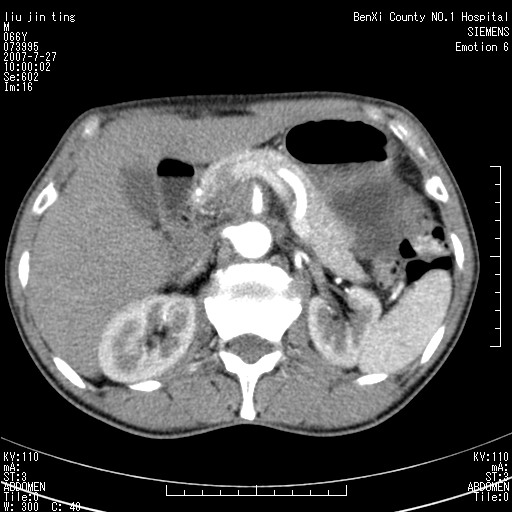

腹痛,背痛,无恶心呕吐,不黄,彩超示胰腺钩癌,ct扫描病灶平扫30-40hu,增强后动脉期40--60hu,静脉期50-68hu,真的是钩突上的么?您要试一试么?

静脉期

沿着肠系膜上动脉呈匍匐性生长的软组织肿块,形态不规则,包绕肠系膜上动脉,呈明显强化,考虑来源于肠系膜的恶性肿瘤

腹腔干至肠系膜上动脉水平肿大淋巴结影可能性大.

沿着肠系膜上动脉呈匍匐性生长的软组织肿块,形态不规则,包绕肠系膜上动脉,呈轻-中度强化,考虑来源于肠系膜的恶性肿瘤。

钩突是正常的,只见腹膜后淋巴结的肿大,考虑淋巴瘤或转移可能。

支持!恶性纤维组织细胞瘤可能,与淋巴瘤及淋巴结转移鉴别(腹主动脉周围清晰,其他部位亦未见明显肿大淋巴结)。

后腹膜肿块,包围血管,考虑淋巴恶性病变,淋巴瘤或转移。